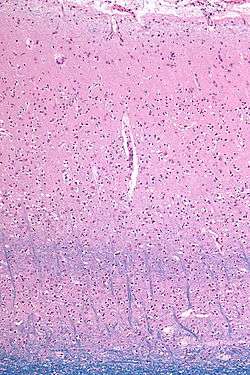

In 1840 Baillarger was the first physician to discover that the cerebral cortex was divided into six layers of alternate white and grey laminae. His name is associated with the inner and outer bands of Baillarger, which are two layers of white fibers of the cerebral cortex. They are prominent in the sensory cortical areas because of high densities of thalamocortical fiber terminations. The outer band of Baillarger is especially prominent in the visual cortex, and is sometimes referred to as the band of Gennari.[2][3]